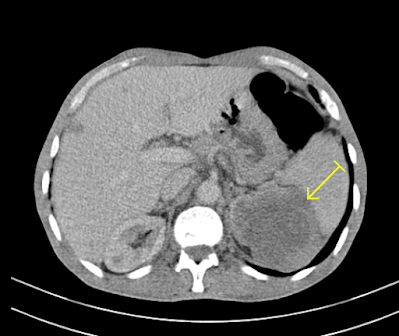

focal lesion in the liver